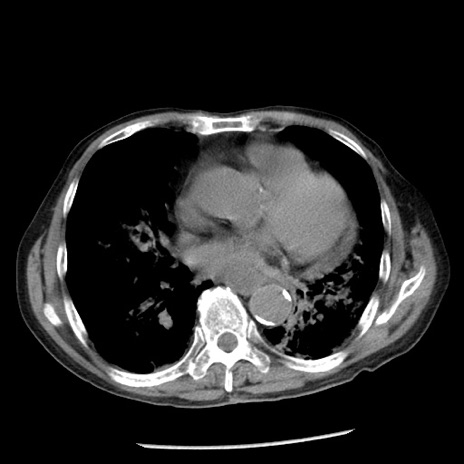

症例26(横断像)

【症例】80歳代男性

【主訴】嘔吐

【現病歴】昨晩2回嘔吐あり、今朝になっても嘔吐あり。来院。

【既往歴】胃潰瘍

【身体所見】意識清明、BT 37.6℃、BP 166/95mmHg、HR 100bpm、SpO2 97%、腹部:平坦・軟、腸蠕動音聴取良好、圧痛なし。

【データ】WBC 21900、CRP 1.46